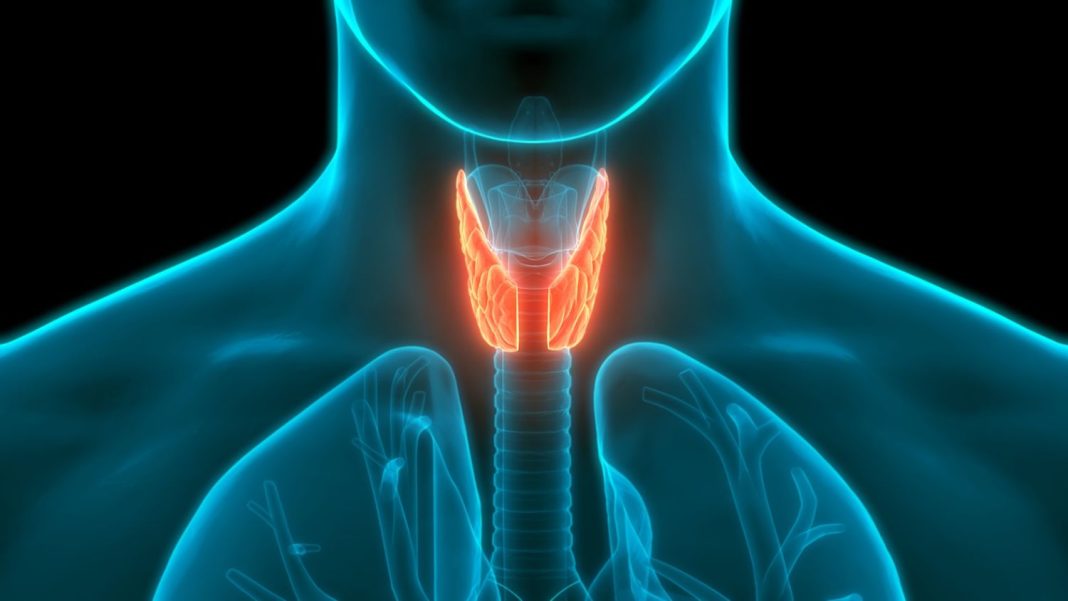

Esta es una glándula cuya morfología asemeja a una mariposa, la cual está ubicada en la el cuello, en la zona central, justo delante de la laringe. Está compuesta por dos lóbulos, que esta unidos en la parte central, conocida como istmo. Cada lóbulo está ubicado cada uno a los lados de la tráquea.

La glándula está compuesta por dos clases de células principales las foliculares y las células C.